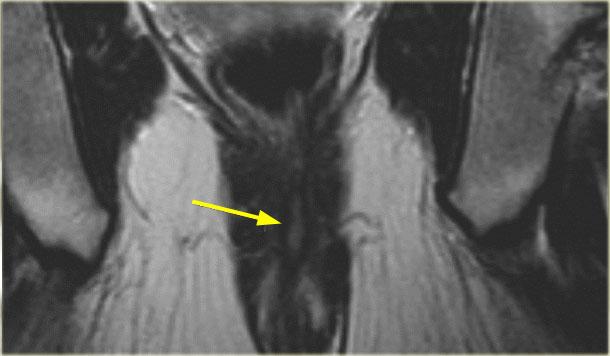

Bên trái là hình ảnh coronal của một bệnh nhân khác có rò liên cơ thắt.

Sử dụng các mũi tên để cuộn qua các hình ảnh.